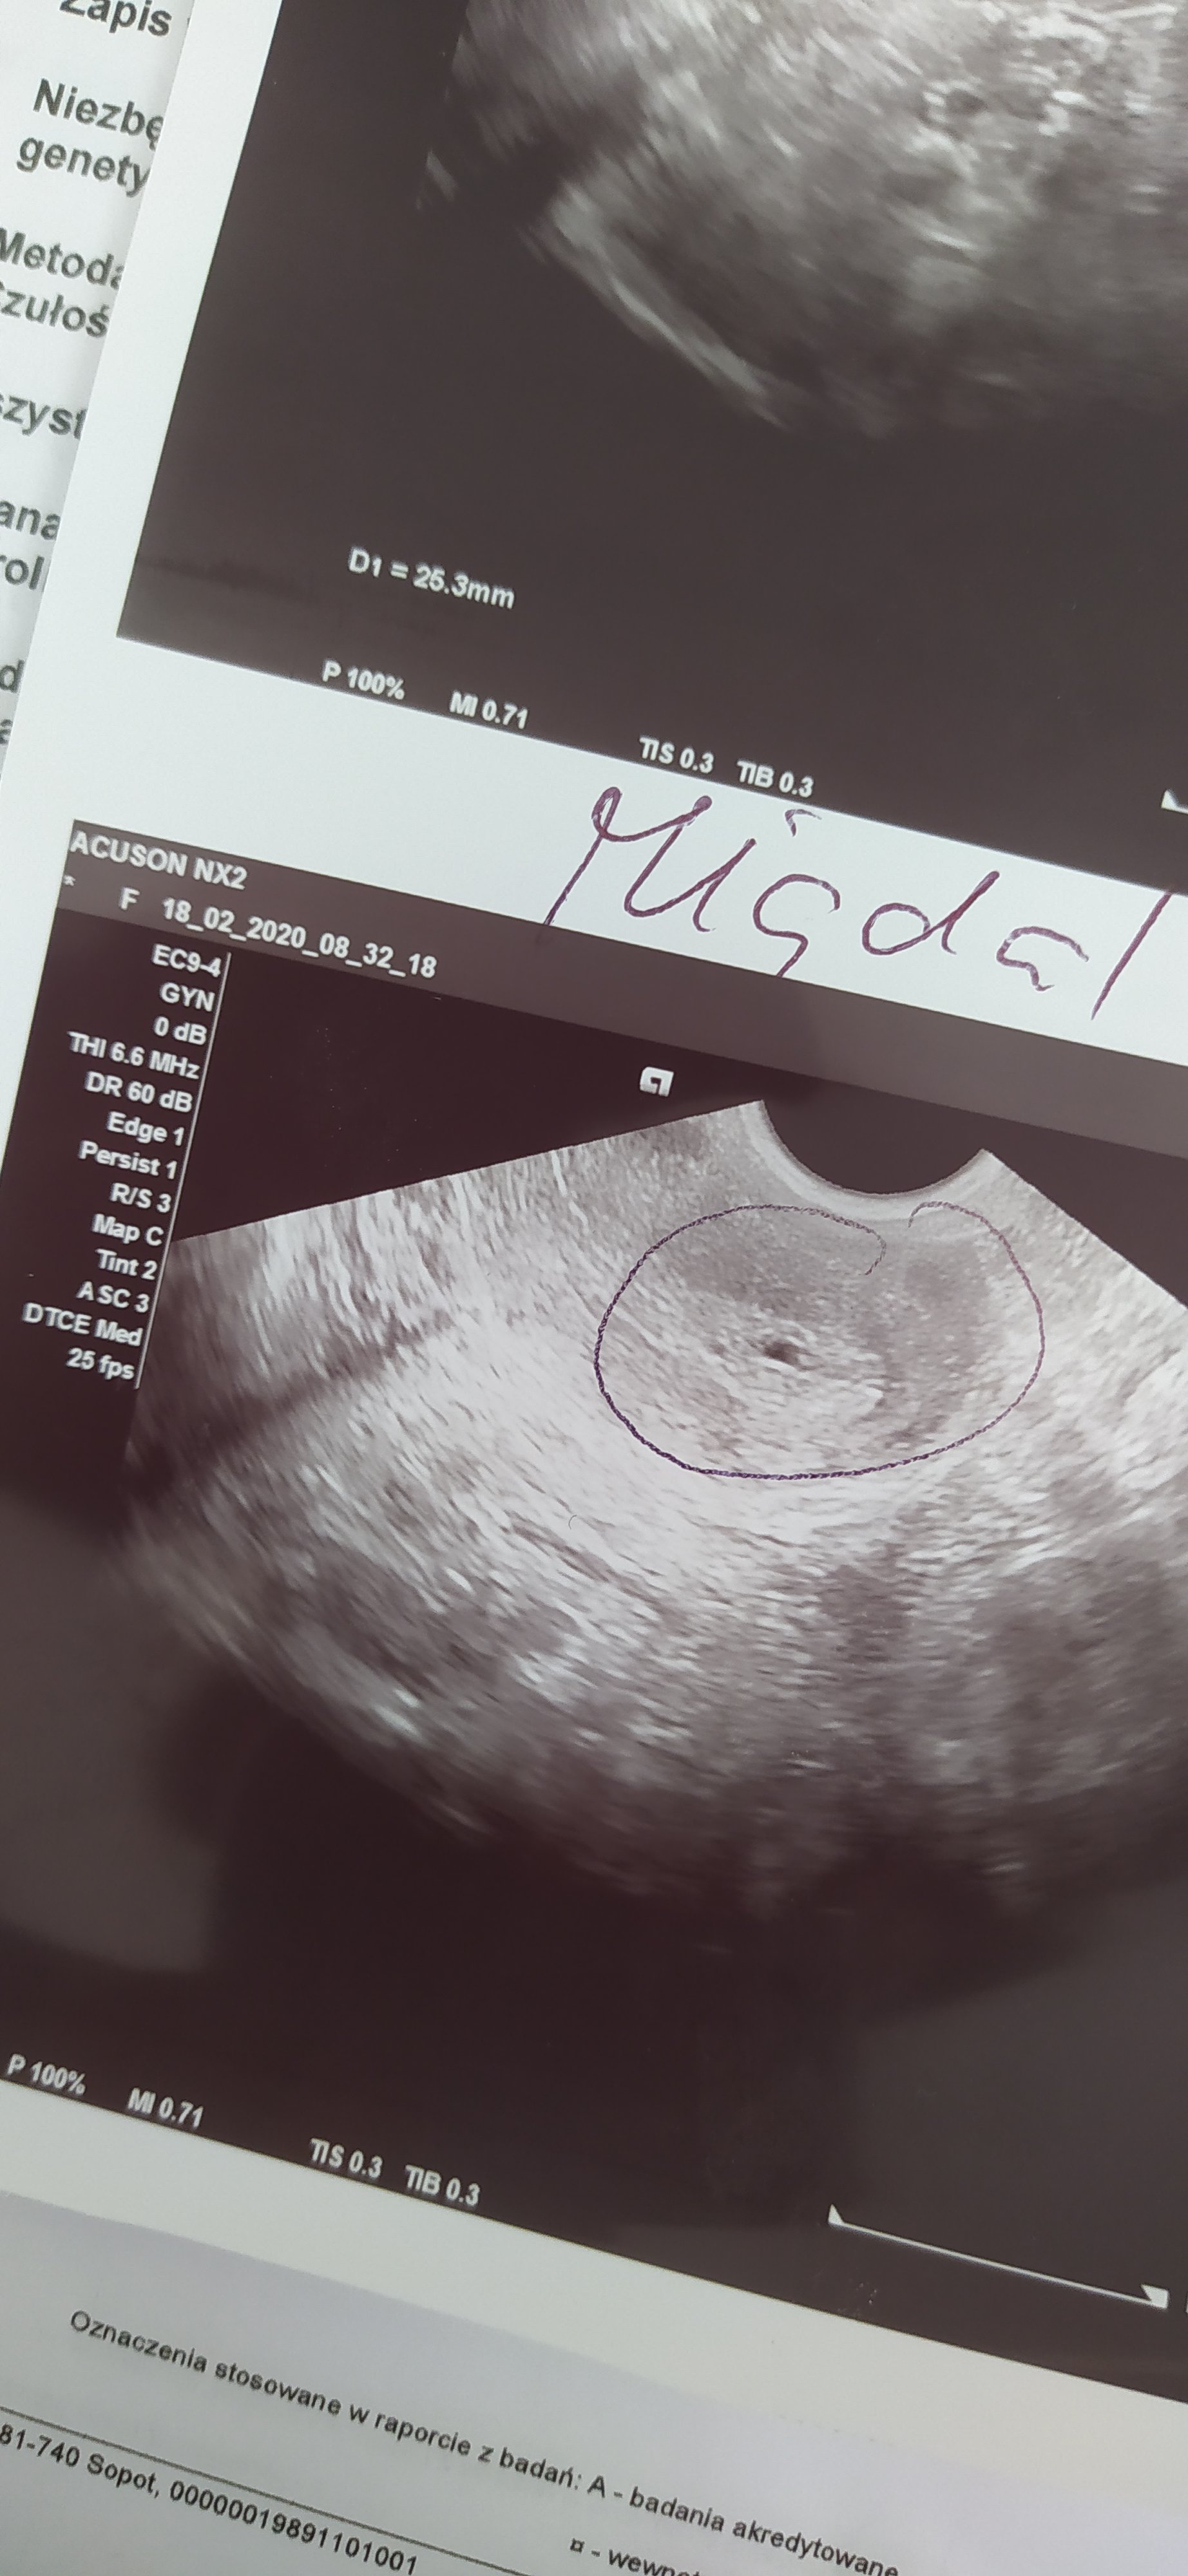

A to moje dzisiejsze usg. Lekarz powiedział, że mogę być w ciąży ale mogę dostać miesiączkę. Pęcherzyk jest malutki, nie widać w nim w środku nic ale w końcu to pęcherzyk w macicy... Delikatnie starał mi się o tym obrazie mówić, bo mówiłam, że boję się naturalnej ciąży z wiadomych względów. No i tak mówi, że może przyjść miesiączka, że mam być dobrej myśli, że może być z tego też zdrowe dziecko i że już mam zacząć o siebie dbać, witaminki zacząć brać. Oczywiście mam zrobić test za kilka dni/betę, na nią dostałam skierowanie no i będzie wszystko wiadomo... Ale chyba jeszcze dzisiaj pójdę na betę, sama nie wiem... Nie wiem co myśleć.

IMG_20200218_092337.jpg